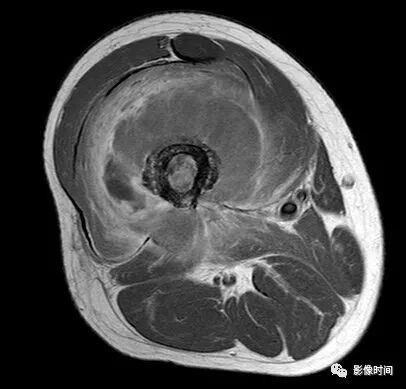

(二)瘤软骨  为肿瘤细胞产生的软骨基质,多来源于软骨类肿瘤,或内有化生瘤软骨成分的其他肿瘤如成软骨型骨肉瘤。瘤软骨为软组织密度,未钙化时,主要通过 MRI 检查显示。

由于瘤软骨多由富含水分及粘多糖的透明软骨构成,故 T1WI 呈偏低信号,T2WI 或 PDWI 呈明显高信号,被低信号的纤维间隔分开呈分叶状(图 24、图 25a-b),增强扫描多呈不均匀分隔状强化(图 25c),主要是纤维间隔强化,瘤软骨强化不明显之故。

图 24  瘤软骨:内生软骨瘤

图 25  瘤软骨:内生软骨瘤